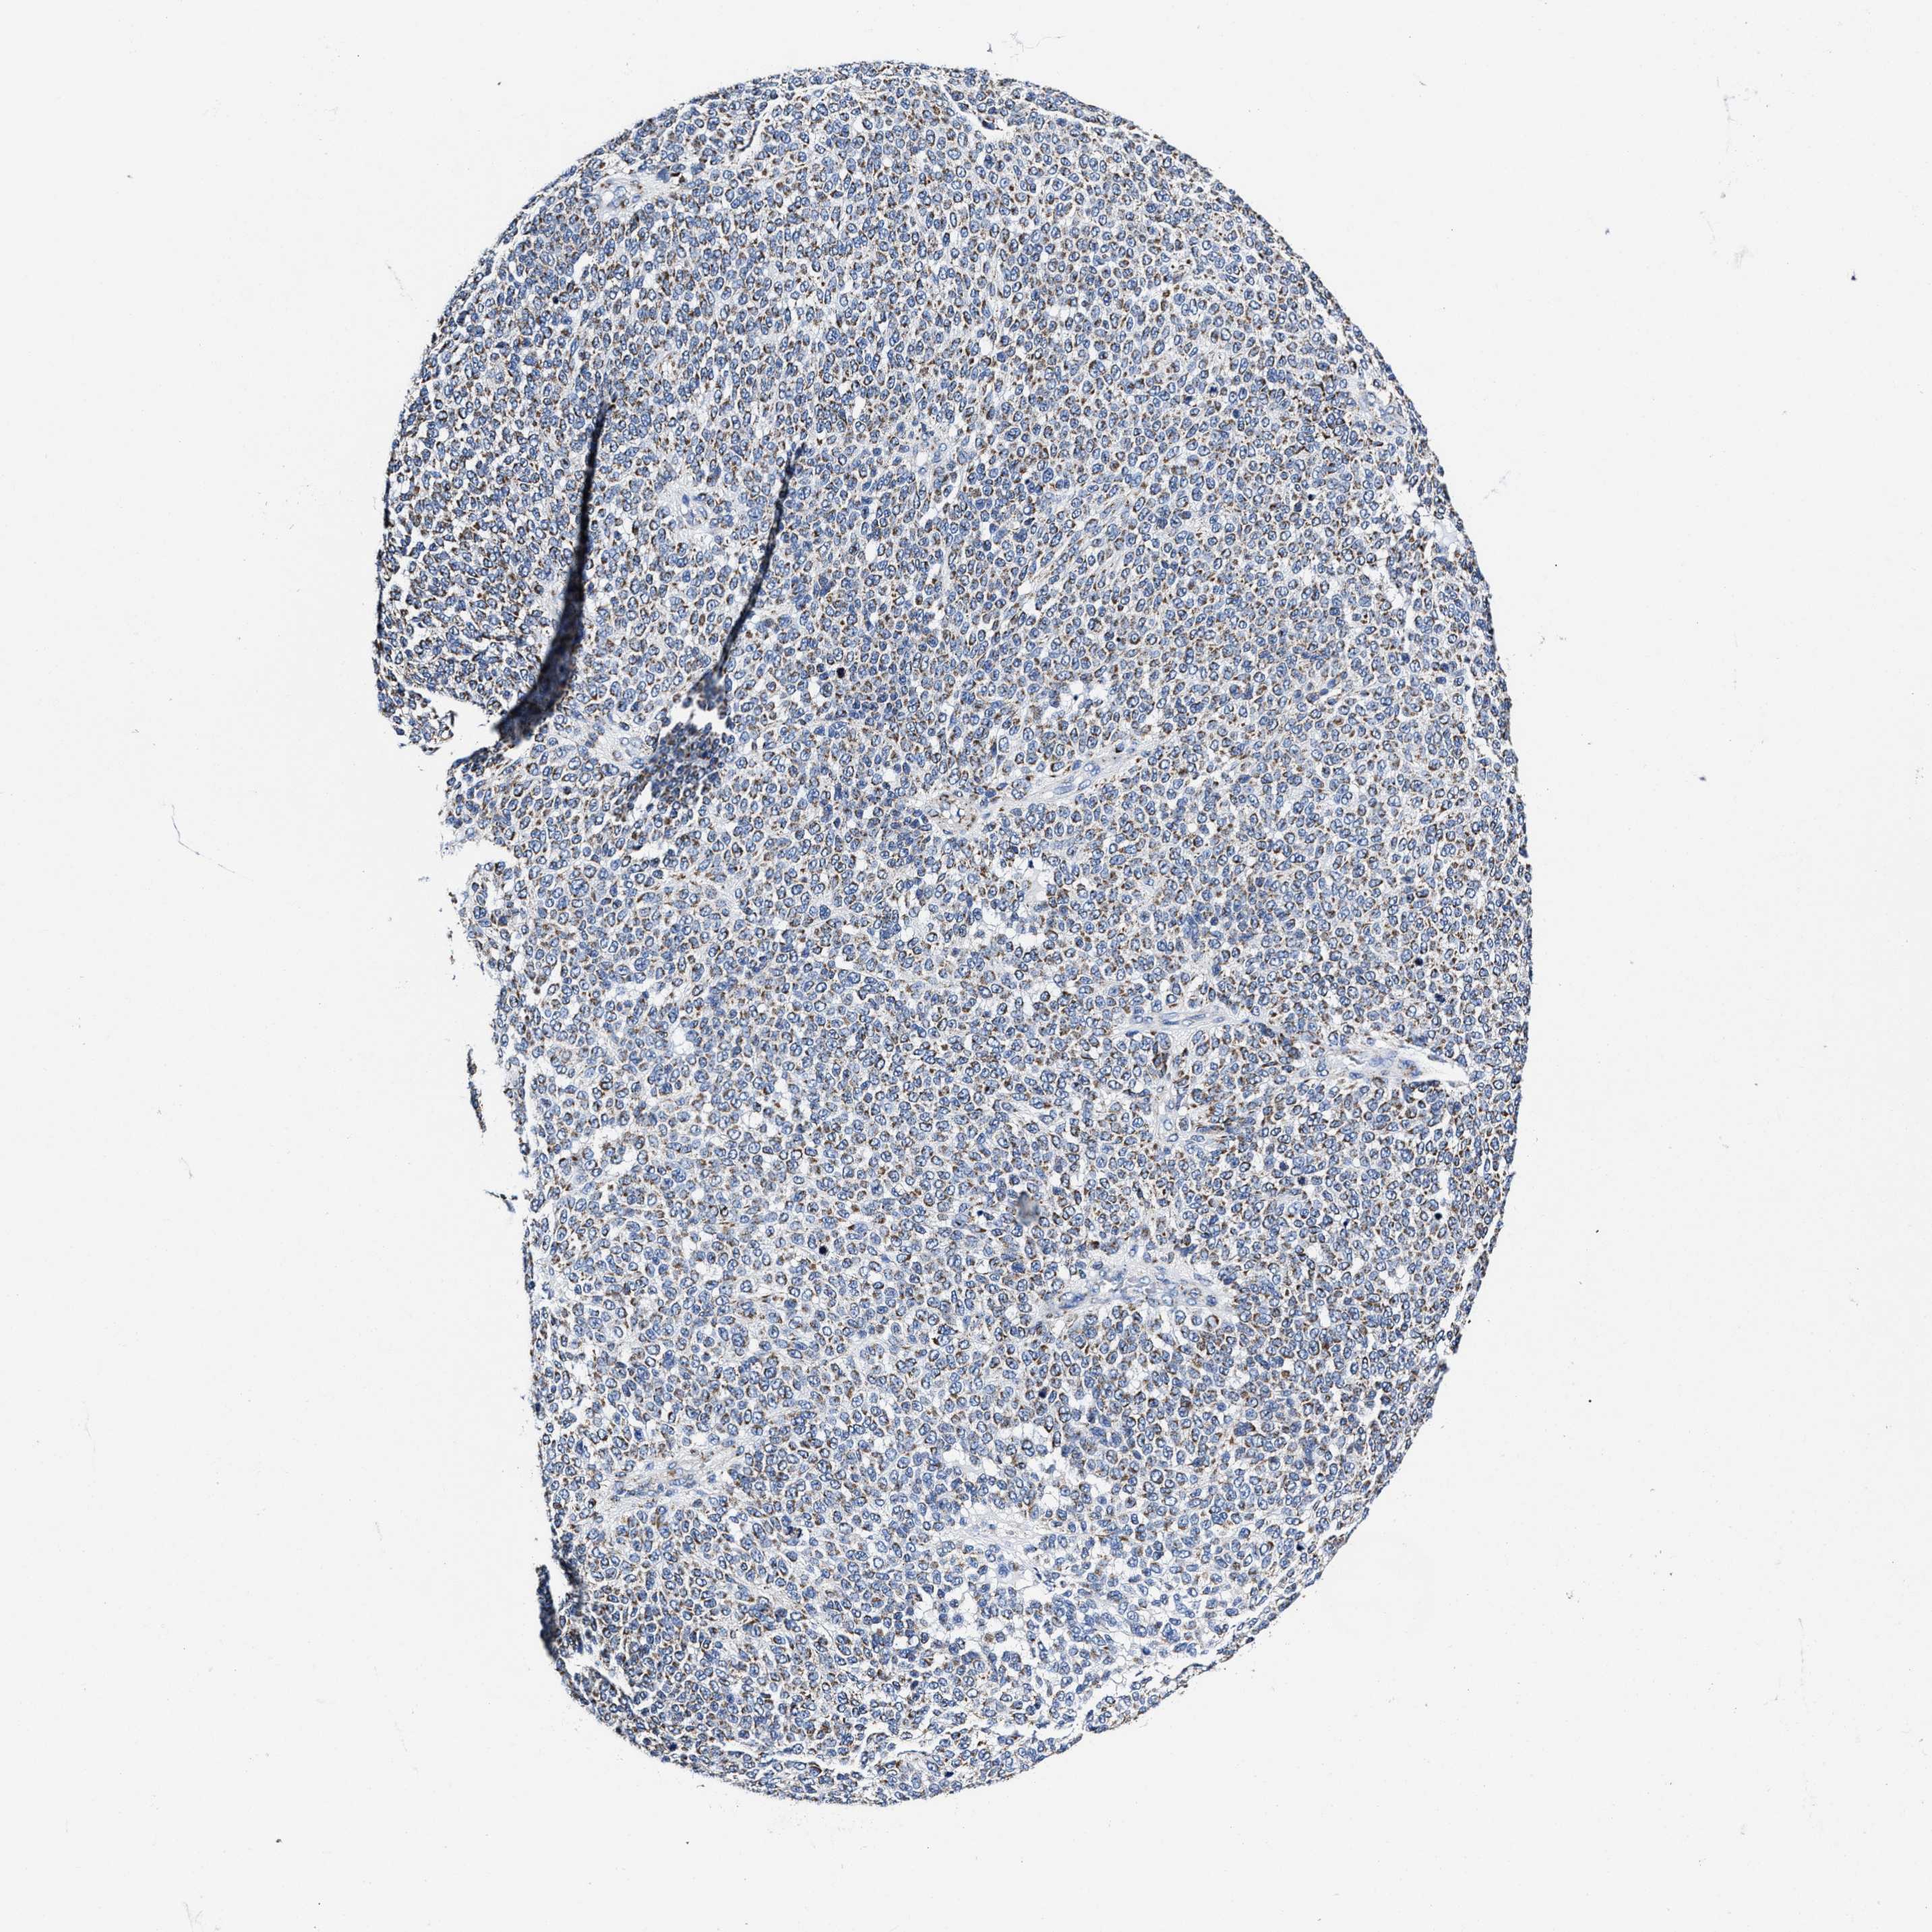

MELANOMA - Protein expressioni

A mouse-over function shows sample information and annotation data. Click on an image to view it in a full screen mode. Samples can be filtered based on level of antibody staining by selecting one or several of the following categories: high, medium, low and not detected. The assay and annotation is described here.

Note that samples used for immunohistochemistry by the Human Protein Atlas do not correspond to samples in the TCGA dataset.

Antibody stainingi

Antibody staining in the annotated cell types in the current human tissue is reported as not detected, low, medium, or high, based on conventional immunohistochemistry profiling in selected tissues. This score is based on the combination of the staining intensity and fraction of stained cells.

Each image is clickable and will lead to virtual microscopy that enables deeper exploration of all samples and also displays staining intensity scores, fraction scores and subcellular localization as well as patient and tissue information for each sample.

Antibody HPA020961

Antibody HPA059109

Staining

High

Medium

Low

Not detected

Intensity

Strong

Moderate

Weak

Negative

Quantity

>75%

75%-25%

<25%

None

Location

Nuclear

Cytoplasmic/membranous

Cytoplasmic/membranous,nuclear

Malignant melanoma, NOS

Malignant melanoma, Metastatic site